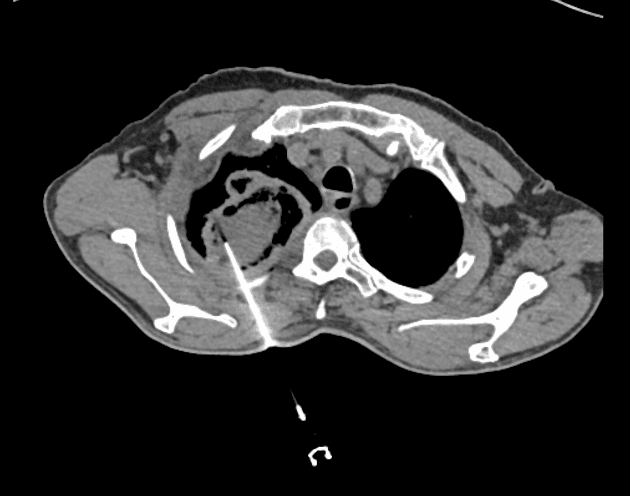

- Tổn thương xâm nhập chủ yếu ở thuỳ trên bên phải.

- Các ổ khí trong tổn thương đặc trưng, không có mức dịch.

- Dấu hiệu vòng ngược (reverse halo) hay còn gọi là dấu hiệu đảo san hô (atoll sign).

- Đã thực hiện phẫu thuật cắt bỏ thuỳ trên bên phải, chẩn đoán xác định là mucormycosis xâm lấn (invasive mucormycosis).

Viêm phổi do nấm xâm lấn là một biến chứng đe dọa tính mạng ở bệnh nhân suy giảm miễn dịch, đặc biệt là những người mắc bệnh ác tính về máu như bạch cầu tủy cấp. Mucormycosis, do các nấm thuộc bộ Mucorales gây ra, là một nhiễm trùng hung hãn, tiến triển nhanh thành hoại tử mô và xâm lấn mạch máu. Về hình ảnh học, dấu hiệu vòng ngược ngày càng được nhận diện như một dấu hiệu gợi ý viêm phổi do nấm xâm lấn, nhất là ở giai đoạn sớm. Mặc dù dấu hiệu này không đặc hiệu hoàn toàn, nhưng sự hiện diện của nó ở bệnh nhân suy giảm miễn dịch cần được đánh giá sâu hơn. Chẩn đoán thường cần xác nhận bằng sinh thiết mô học, và điều trị bao gồm dùng thuốc kháng nấm sớm như amphotericin B, cùng với cắt bỏ ngoại khoa nếu khả thi. Các chẩn đoán phân biệt bao gồm các nhiễm trùng cơ hội khác như aspergillosis, cryptococcosis và viêm phổi do pneumocystis, những bệnh này có thể có hình ảnh học trùng lặp.